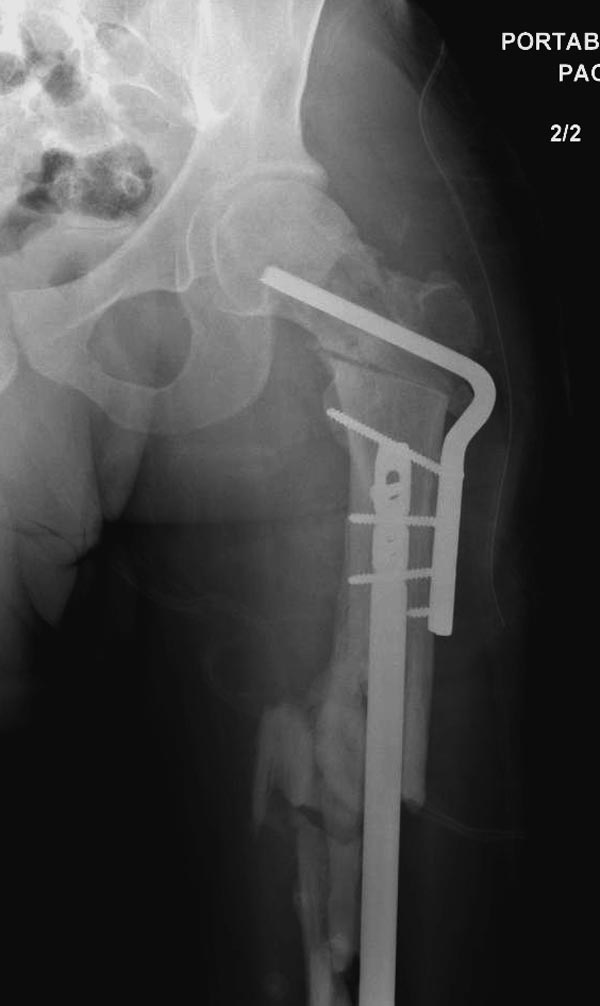

Здесь выставлен ренгенограммы больного, ему 21, травму получил в результате высокоскоростной погони на украденной машине, которая закончилась смертью трех остальных “боевых комрадов”. Начатую коллегой открытую операцию на шейке пришлось закончить мне, установкой винтов и ретроградной фиксацией бедра. Выписка в обычное сроки и наблюдался амбулаторно. Каждый раз напоминали о возможности осложнений ввиде несращения! По истечению 4 месяцев появились признаки варусной деформации. На СТ срезах несращение шейки и бедра. Риминг, замена на более толстый гвоздь и вальгусная остеотомия.

Сразу скажу, что пациент вчера (8.04) прооперирован - артротомия, остеосинтез мыщелков большеберцовой кости канюлированными винтами, открытая репозиция отломков бедренной кости, ретроградный БИОС, остеосинтез надколенника (центральных его отломков) спицами с проволочной петлей. Двухкратная попытка закрытой репозиции шейки на операционном столе после синтеза бедра - абсолютно неэффективна. Учитывая продолжительность и травматичность операции, шейка отложена на 2-й этап. Плечо наверное на 3-й (если вообще делать). Снимки постараюсь предоставить, но чуть позже.